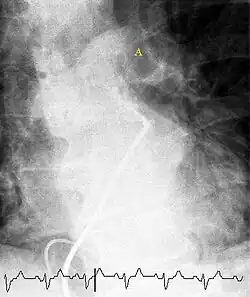

CT pulmonary angiography

CT pulmonary angiography (CTPA) is a pulmonary angiogram obtained using computed tomography (CT) with radiocontrast rather than right heart catheterization. Its advantages are that it is accurate, it is non-invasive, it is more often available, and it may identify other lung disorders in case there is no pulmonary embolism. The accuracy and non-invasive nature of CTPA also make it advantageous for people who are pregnant.[61]

-

On CT scan, pulmonary emboli can be classified according to the level along the arterial tree. -

Segmental and subsegmental pulmonary emboli on both sides -

CT pulmonary angiography showing a "saddle embolus" at the bifurcation of the main pulmonary artery and thrombus burden in the lobar arteries on both sides

Pulmonary embolism (white arrow) that has been long-standing and has caused a lung infarction (black arrow) seen as a reverse halo sign

Assessing the accuracy of CT pulmonary angiography is hindered by the rapid changes in the number of rows of detectors available in multidetector CT (MDCT) machines.[62] According to a cohort study, single-slice spiral CT may help diagnose detection among people with suspected pulmonary embolism.[63] In this study, the sensitivity was 69% and specificity was 84%. In this study which had a prevalence of detection was 32%, the positive predictive value of 67.0% and negative predictive value of 85.2%. However, this study's results may be biased due to possible incorporation bias, since the CT scan was the final diagnostic tool in people with pulmonary embolism. The authors noted that a negative single-slice CT scan is insufficient to rule out pulmonary embolism on its own. A separate study with a mixture of 4-slice and 16-slice scanners reported a sensitivity of 83% and a specificity of 96%, which means that it is a good test for ruling out a pulmonary embolism if it is not seen on imaging and that it is very good at confirming a pulmonary embolism is present if it is seen. This study noted that additional testing is necessary when the clinical probability is inconsistent with the imaging results.[64] CTPA is non-inferior to VQ scanning, and identifies more emboli (without necessarily improving the outcome) compared to VQ scanning.[65]